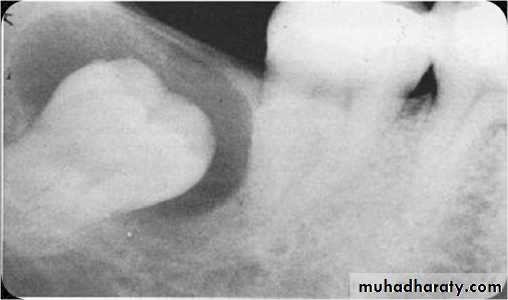

Cysts (abnormal, closed-walled sac present in or around tissue): usually X-ray detected and removed before they enlarge and destroy bone tissue. Some types are:A- Dentigerous: cystic sac containing a tooth or tooth bud particle.